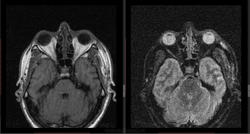

- https://radiomed.ru/sites/default/files/styles/case_slider_image/public/user/16807/3_22.jpg?itok=i_xXDvqx

- https://radiomed.ru/sites/default/files/styles/case_slider_image/public/user/16807/4_12.jpg?itok=JIJx1gcZ

дифференциальная диагностика ganglion ,нодулярный фасциит,нейрофиброма,дерматофиброма